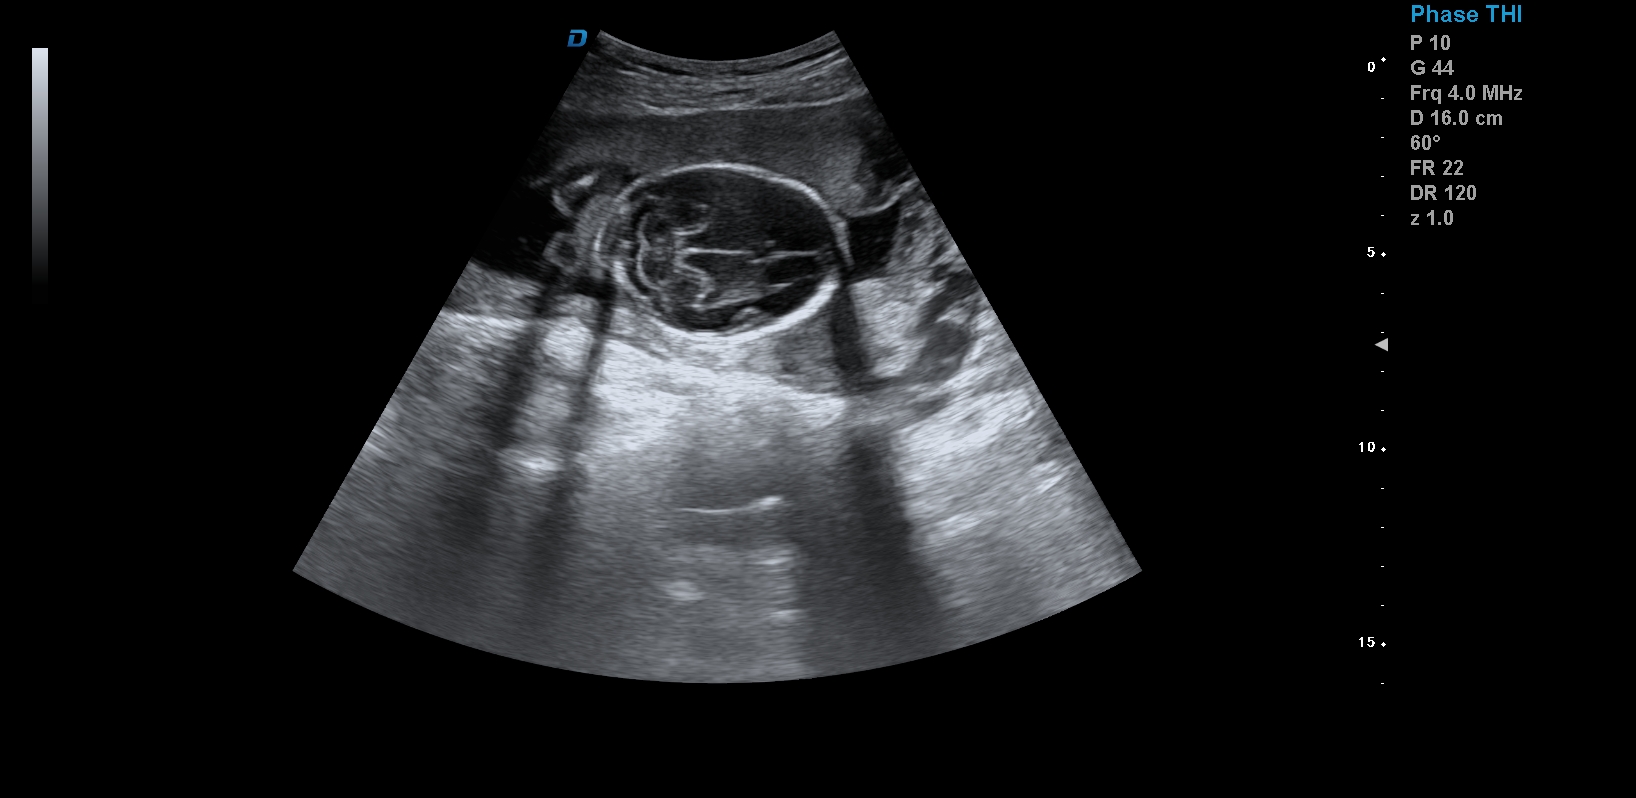

首先,四維彩超檢查是采用高清晰度的彩超儀對胎兒進(jìn)行各個心臟器官及組織的一次全面檢查,可以立體顯示胎兒的發(fā)育情況,胎兒在子宮內(nèi)的任何狀態(tài)都可以觀察到。對胎兒畸形能夠早診斷,及時地做出相應(yīng)的措施,以達(dá)到優(yōu)生優(yōu)育的標(biāo)準(zhǔn)。

四維彩超不但成像清晰,更是在三維的基礎(chǔ)之上附加時間這個矢量。這就在排畸的同時能時刻觀察寶寶在宮內(nèi)的一舉一動,吃手指、打哈欠、吮吸……寶寶在宮內(nèi)憨態(tài)可掬,讓孕媽媽母愛井噴,幸福不已。這也是孕媽媽們選擇四維的主要原因,試想,誰不想在辛苦懷孕期間提前看一看自己寶寶的模樣呢?

1、四維彩超是目前先進(jìn)的彩色超聲技術(shù).能直觀立體現(xiàn)實人體器官動靜態(tài)三維結(jié)構(gòu),一定程度上提高臨床診斷的準(zhǔn)確性。

3、清晰成像:采用先進(jìn)的超聲成像技術(shù),擁有高清晰,高分辨率、高精確度優(yōu)點,能清晰看到包括生殖器、內(nèi)臟器官在內(nèi)的胎兒的各個部位發(fā)育情況.